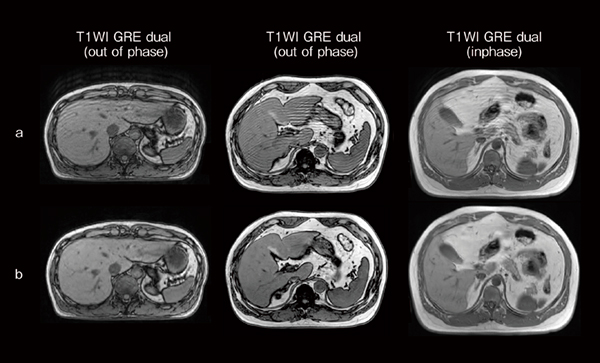

同じく体動による画質劣化を改善する「Navigated StillShot(ナビゲーティッド スティルショット)」という機能があります。これは,カメラの代わりに体動を検出するためのナビゲーターパルス(Motion Navi) を撮像シーケンス内に付加し,体動の基準値に対するナビゲーターエコーの値が一定の閾値を超える場合に体動データを除去します。図3に腹部の息止め不良例を想定したボランティア画像を示しますが,Navigated StillShotによる再構成画像では,体動アーチファクトが軽減していることがわかります。このようにMRI検査中に咳やくしゃみ,不随意運動による突発的な体動などが生じた場合に,画像再構成処理によって体動アーチファクト低減を支援することができますので,再撮像頻度の低減に期待ができます。

図3 体動アーチファクト画像(a)とNavigated StillShotによる再構成画像(b)

腹部の息止め不良例を想定した腹囲の異なるボランティア画像(a)を撮像後,Navigated StillShotで画像再構成をすることにより,体動アーチファクトを低減した画像(b)を生成することができる。